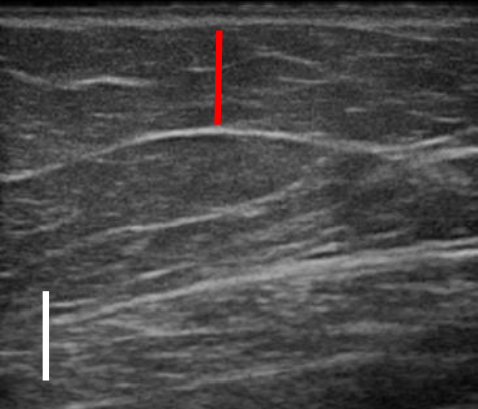

위 사례도 초음파 비교 사진을 보도록 할게요.

트루스컬프 아이디 시술 전, 12주 후

초음파를 비교한 사진입니다.

위 사례의 경우 지방량이 워낙 많다 보니 시술 후 겉으로 드러난 변화는 적었으나 실제로 감소한 지방량은 상당히 많았습니다.

시술 전과 비교했을 때 약 31% 정도 지방이 감소했습니다.

복부, 옆구리살이 너무 많은 경우 실제 눈에 보이는 것보다 내부에 쌓여있는 지방이 두터운 경우가 많아 시술을 해도 큰 변화를 보이지 않는 경우가 많은데요. 실제로 시술 후 큰 변화가 없어 실망하는 분들도 많지만 위와 같이 초음파 검사를 통해 속을 들여다보면 상당 부분 지방이 감소한 것을 확인할 수 있습니다.